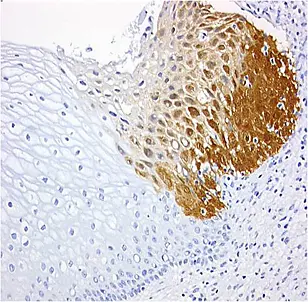

Gewebeschnitt vom Gebärmutterhals: Die braune Färbung ist ein Indiz für bösartig veränderte Zellen. Quelle: mtm laboratories

Der Firmengründer Prof. Dr. Magnus von Knebel Doeberitz arbeitet im Universitätsklinikum Heidelberg und leitet zugleich im Deutschen Krebsforschungszentrum die Klinische Kooperationseinheit „Angewandte Tumorbiologie“. Gemeinsam mit Dr. Christina von Knebel Doeberitz und Dr. Rüdiger Ridder konnte er Ende der 1990er-Jahre Risikokapitalgeber von ihrer Geschäftsidee überzeugen. Auf der Basis der p16-Patente, an denen das DKFZ mit 20 Prozent beteiligt ist, entwickelten die mtm-Forscher einen immunhistochemischen Test, der in Gewebeschnitten zuverlässig fortgeschrittene Vorstufen von Gebärmutterhalskrebs anzeigt. Das Verfahren beruht auf dem Nachweis der erhöhten Produktion des Krebsproteins p16. Bei chronischer Infektion mit Hochrisikotypen des humanen Papillomvirus bilden die Zellen der Gebärmutterhalsschleimhaut diesen Biomarker, der die Transformation zu bösartigen Krebszellen anzeigt. Mit dem CINtec ® p16- Test, den mtm 2007 weltweit auf den Markt brachte, werden die transformierten Zellen deutlich farbig dargestellt. Damit kann der Pathologe selbst kleinste Krebsherde von wenigen Zellen sicher zu erkennen.